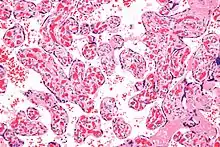

| Micrograph of a chorangiosis. H&E stain. | |

Chorangiosis is a placental pathology characterized by an abundance of blood vessels within the chorionic villi.

It is diagnosed by a microscopic examination of the placenta.

Commonly used criteria from Altshuler[2][3] are: "a minimum of 10 villi, each with 10 or more vascular channels, in 10 or more areas of 3 or more random, non-infarcted placental areas when using a ×10 ocular." The Altshuler criteria are not theoretically rigorous, as they do not define the area. Normal villi have up to five vascular channels.[3]